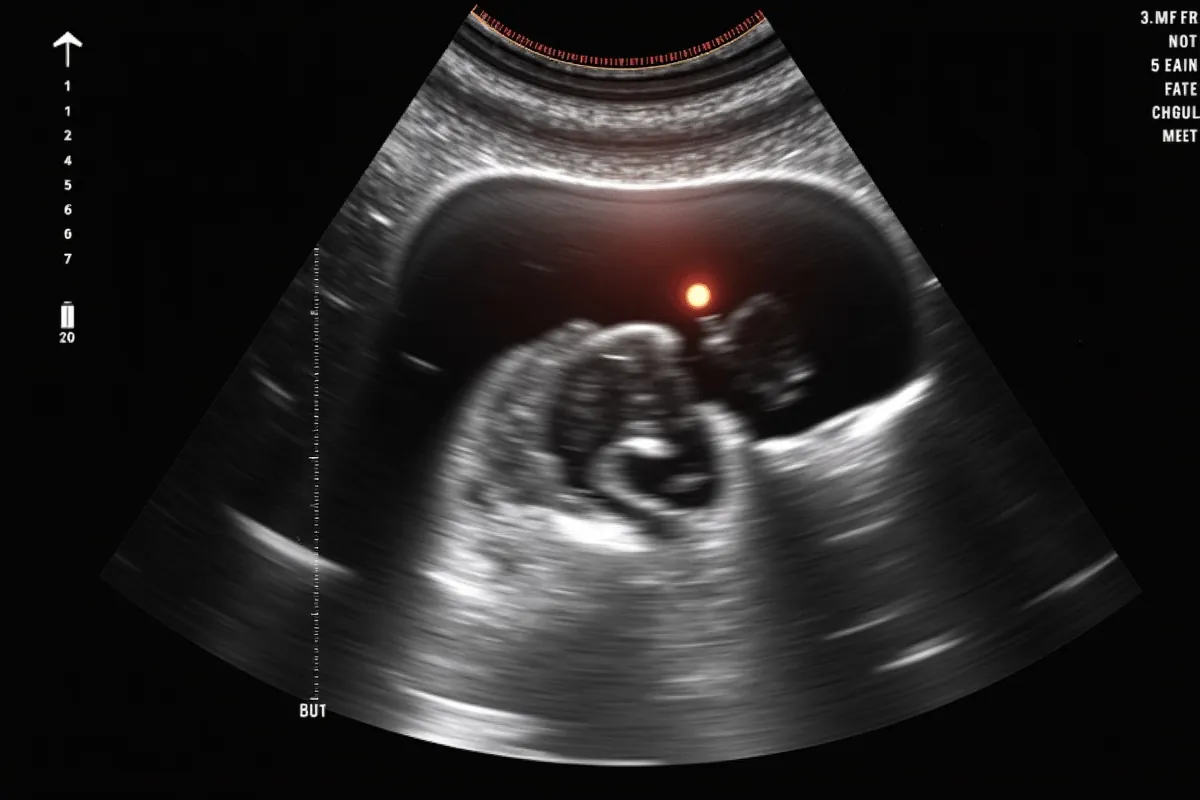

Wymiary główki płodu są zazwyczaj dokładnie mierzone podczas badań ultrasonograficznych. Obwód głowy może odgrywać kluczową rolę w diagnostyce prenatalnej. Na przykład, gdy istnieje podejrzenie zespołu Downa, lekarze mogą zlecić dodatkowe badania w celu wykluczenia ryzyka trisomii 21. chromosomu. Statystyki pokazują, że zespół Downa występuje w około 1 na 700 urodzonych dzieci.

Dlatego tak istotna jest dokładna analiza wyników USG. Konsultacja z lekarzem umożliwia precyzyjną ocenę ryzyka oraz wskazanie ewentualnych dalszych kroków diagnostycznych.

Diagnostyka prenatalna, szczególnie w kontekście zespołu Downa, obejmuje szereg badań, które pomagają ocenić ryzyko wystąpienia tej wady genetycznej. Wśród najważniejszych metod znajduje się ultrasonografia, a zwłaszcza USG połówkowe. Dzięki niemu specjaliści mogą szczegółowo ocenić anatomię płodu oraz zmierzyć przezierność karkową. W przypadku wykrycia jakichkolwiek nieprawidłowości, lekarze mogą zlecić dodatkowe badania, takie jak test PAPP-A, który analizuje poziom specyficznego białka w krwi matki.

Warto także zaznaczyć, że ognisko hiperechogeniczne w sercu występuje u około 5% płodów w połowie ciąży i może być dodatkowym wskaźnikiem ryzyka. Kluczowe w diagnostyce prenatalnej jest, aby przyszli rodzice byli dobrze poinformowani o dostępnych opcjach, możliwych wynikach oraz następnych krokach w procesie diagnostycznym. Rzetelne informacje i konsultacje z lekarzem pozwalają na podejmowanie świadomych decyzji przez przyszłych rodziców.